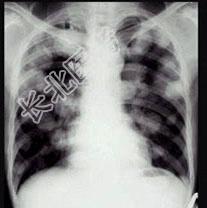

- 单项选择题男,45岁, HBV阳性十年,胸痛一月伴咳嗽, 咯血一天,胸片如图, 选择最可能的诊断 ( )

E、肺转移癌